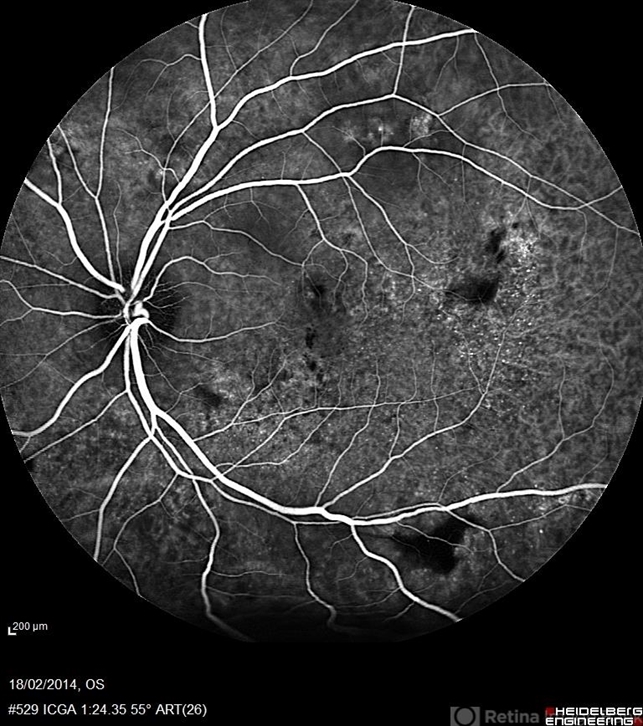

- indocyanine green (ICG) angiography, multifocal central serous chorioretinopathy (CSCR)

- ICG (Early Phase) a 38-year-old man with multifocal CSR and inferior exudative retinal detachment on both eyes (Harada Syndrome).